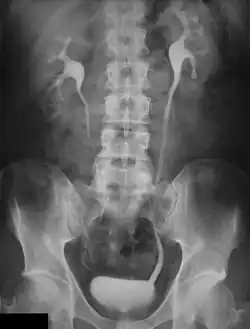

Pyelogram (or pyelography or urography) is a form of imaging of the renal pelvis and ureter.[1]

An intravenous pyelogram (IVP), also called an intravenous urogram (IVU), is a radiological procedure used to visualize abnormalities of the urinary system, including the kidneys, ureters, and bladder. Unlike a kidneys, ureters, and bladder x-ray (KUB), which is a plain (that is, noncontrast) radiograph, an IVP uses contrast to highlight the urinary tract.

An injection of X-ray contrast medium is given to a patient via a needle or cannula into the vein,[7] typically in the antecubital fossa of the arm. The contrast is excreted or removed from the bloodstream via the kidneys, and the contrast media becomes visible on X-rays almost immediately after injection. X-rays are taken at specific time intervals to capture the contrast as it travels through the different parts of the urinary system.[7] At the end of the test, a person is asked to pass urine and a final X-ray is taken.[7]

Immediately after the contrast is administered, it appears on an X-ray as a 'renal blush'. This is the contrast being filtered through the cortex. At an interval of 3 minutes, the renal blush is still evident (to a lesser extent) but the calyces and renal pelvis are now visible. At 9 to 13 minutes the contrast begins to empty into the ureters and travel to the bladder which has now begun to fill. To visualize the bladder correctly, a post micturition X-ray is taken, so that the bulk of the contrast (which can mask a pathology) is emptied.